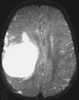

Desmoplastic infantile ganglioglioma